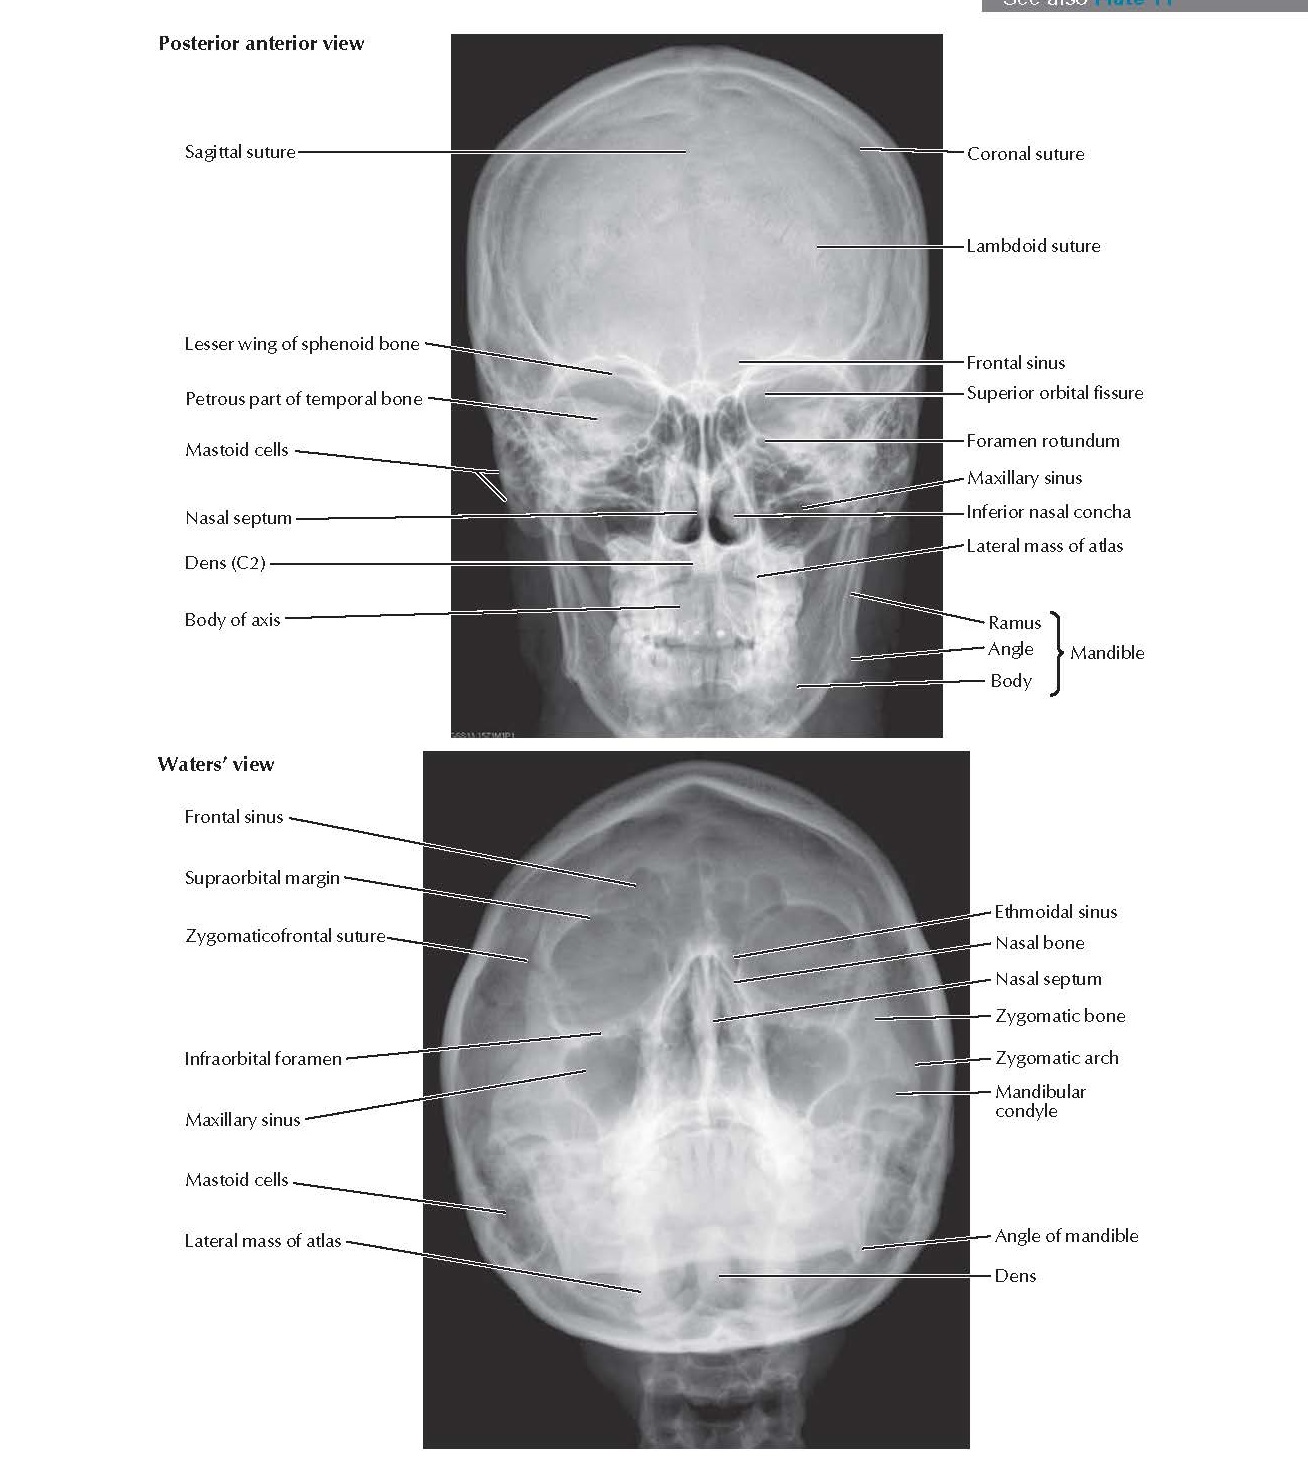

Skull Radiographs Anatomy pediagenosis Skull Anatomy Xray    in this review, after a brief anatomical description of the skull, the imaging methods used in the diagnosis of skull pathologies and the main. The skull rests on the superior aspect of the vertebral column.   the skull is the skeletal framework of the head of vertebrates formed by the cranium. It is composed of 22 separate bones divided. Skull Anatomy Xray.